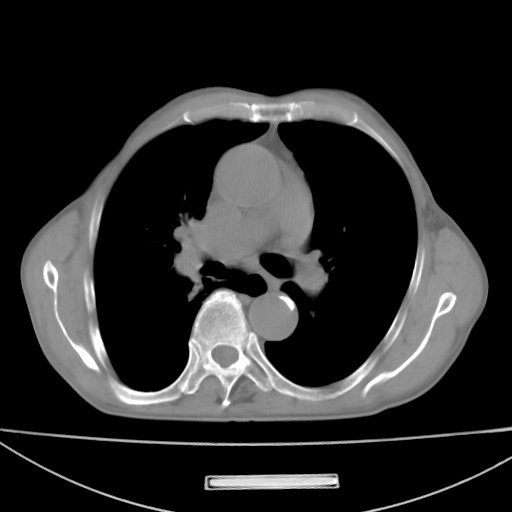

标题: CT13796:请会诊右上费病变!

患者男80岁,反复咳嗽多年,咳喘伴咯血1月

右上肺周围型肺癌伴肺门淋巴结转移.右上肺继发型肺结核.

右上肺周围型肺癌伴肺门淋巴结转移

右肺上叶占位性病变,考虑周围型肺癌,肺门淋巴结转移。要是能提供更多的临床资料就好了,以供鉴别诊断。

右肺尖周围型肺癌伴肺门淋巴结肿大

右肺上叶占位性病变,考虑周围型肺癌,肺门淋巴结转移。

右上肺周围型肺癌伴肺门、纵膈淋巴结转移

考虑为:右肺上叶肺癌伴阻塞性肺炎、右肺门及纵膈淋巴结转移。